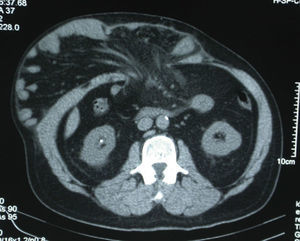

Technically, abdominal hernia or incisional hernia with loss of domain was defined as having more than 50% of the abdominal cavity contents outside the abdomen (Fig. 1). In most cases, this was determined with a preoperative abdominal CT scan (Fig. 2). Once they had been selected, the patients were referred for pre-anesthetic assessment and scheduled for hospitalization prior to the surgical intervention.

After 2 weeks of insufflation, the abdominal wall was examined by evaluating the muscle tension exhibited on the side of the abdomen in order to verify that this was becoming sufficiently relaxed. In some cases, the patients underwent a control CT scan (Fig. 4), but this was not done systematically because the follow-up of the progression was mainly clinical. Patients were considered fit for surgery when the lateral abdominal musculature was completely distended.